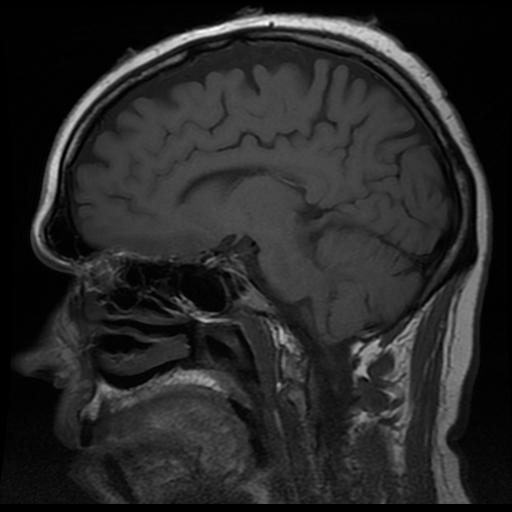

Anterior temporal lobectomy (ATL) is a common approach to seizure control with a proven therapeutic track record. However, as many as 7% of patients experience postoperative psychiatric disorders [1]. For a patient who experiences preoperative emotional impairment (such as can be the case following status epilepticus), even on the scale of minutes, and comes to recognize it as such, the experience can inspire an obsessive yet warranted desire for information pertaining to the possible postoperative side effects of ATL. By impairment I generally mean a deficit of response to a stimuli such as feeling a profound indifference towards a loved one following a medical trauma [2] rather than a miss-assignment of emotion to a stimulus (a greater impairment but not one I address). In personal experience in an American hospital (the author has left mesial temporal sclerosis), preoperative assessment for vulnerability to emotional impairment is not evaluated nor is information drawn from research on others discussed with the patient (see [3] for an example of ideal procedures in France)

Emotional recognition functions in the brain are more complex and region specific than has been previously assumed [4]. Discernment of the valence of other’s response to stimuli is lateralized across hemispheres but the extent of this lateralization for different emotions varies between individuals [5]. Patients suffering from amygdala damage can have inconsistent patterns of recognition deficits [6]. Particular attention should be paid to the amygdala in preoperative assessment of risks, as it is especially important in linking affect (esp. negative affect) to stimuli from the environment or from individuals, and it has strong connections to sensory cortex [7].

In addition to recognition of external displays of emotion (such as from music or the facial expressions of others) internal perceptions of fear, happiness, and other emotions have been mapped with direct electrical stimulus to brain areas and found to originate in the amygdala with perceptions varying between the left and right hemisphere [3]. Thus the potential side effects of an ATL, both in accuracy of recognition and/or intensity of personal feeling can vary by the side of the brain operated on and from patient to patient thereby justifying a patient’s desire for more information.